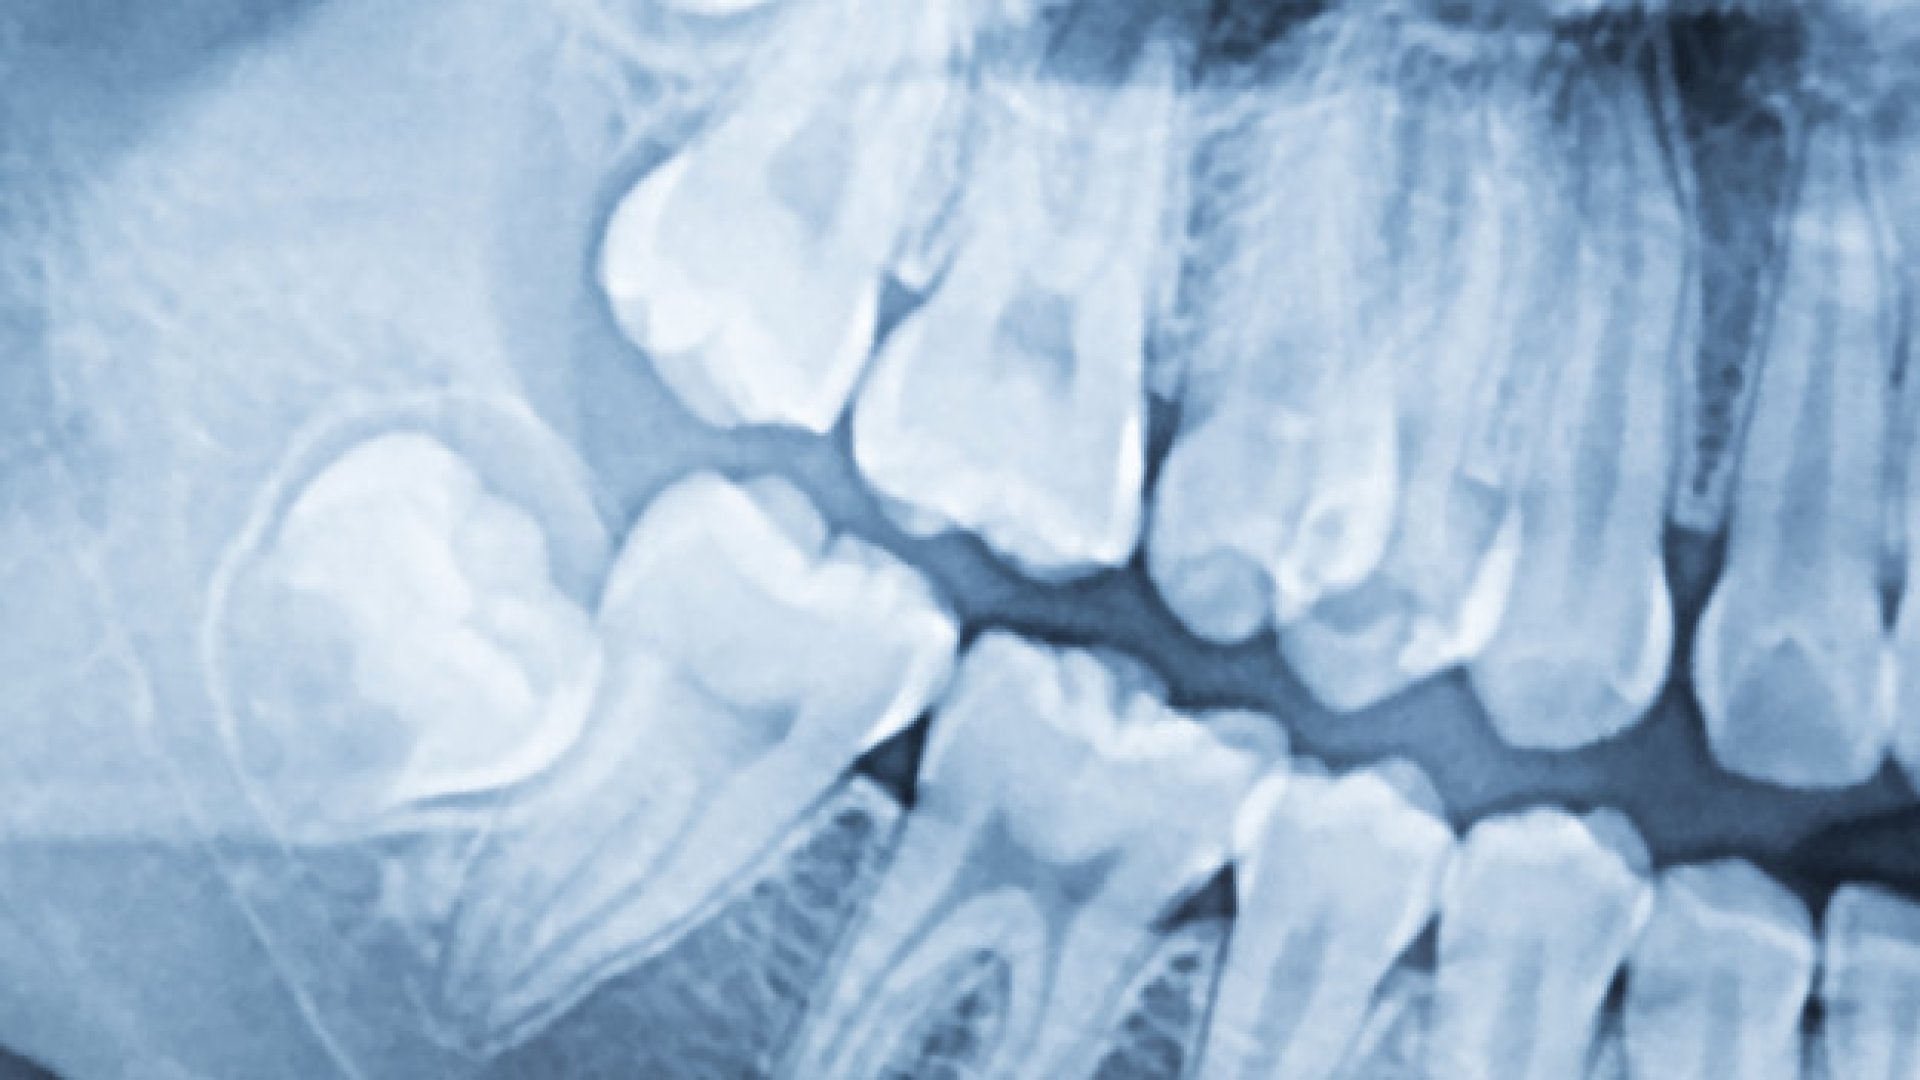

Dental implantation can be daunting at first because it involves several steps and is lengthy, but in the long run it is the most cost-effective solution. First and foremost, we will perform a thorough dental diagnosis and screening before implanting a dental implant. We will assess whether you have any other dental problems apart from the missing tooth. If there is, we will treat the problem first to ensure that the dental implant procedure is as risk-free as possible, avoiding inflammation and infection. The diagnostics will also help us to decide whether bone grafting is necessary before the dental implant is placed. If so, treatment will start with the bone grafting and only then will we start the dental implant procedure.

Dental implant placement is a complex procedure, as the implant itself is placed in the jawbone. Once this is done, there is a healing period of 3-6 months after the dental implant is placed, during which the body and tissues have to accept the implant. Once this is done, the implant is released from under the gum and a gum shaping screw is placed into the implant to shape the gum aesthetically and allow for easy insertion of a dental crown later. Whole tooth implant placement can be lengthy due to the healing time, but each patient's placement, treatment and healing process is personalised.